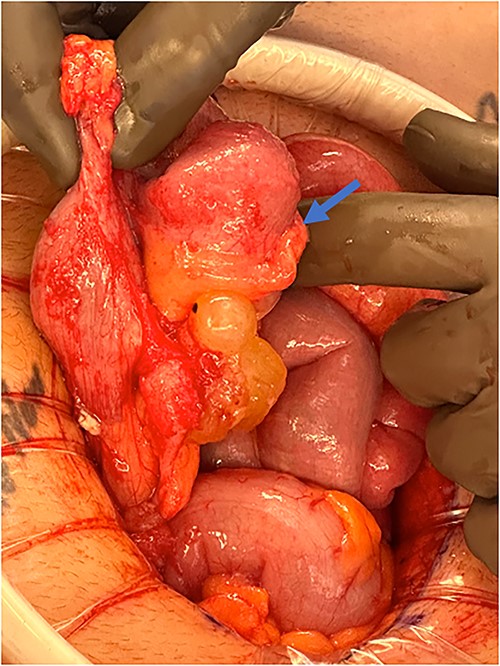

An exploratory laparotomy with a midline incision was performed. Upon inspection of the abdominal cavity, there was no evidence of metastatic disease to the peritoneum, omentum, or liver. A perforated mucinous mass with mucinous collection was identified in the right lower quadrant by the appendix with an additional mucinous collection in the pelvis. Given the appendiceal and cecal involvement, the decision was made to perform a right hemicolectomy and primary anastomosis. Given that this was favored to be a malignant process intraoperatively, the decision was made to perform a right hemicolectomy over a limited ileocolic resection. Lymph nodes were also included due to the extent of the surgical resection. The specimens were sent to pathology. The abdomen was further inspected and subsequently closed (Figs 3–5). The patient tolerated the procedure well, was extubated in the operating room, and recovered in the post-anesthesia care unit in stable condition. The patient was observed postoperatively and was discharged home on postoperative Day 8. The duration of follow-up is 4 months without clinical concerns during follow-up. The final pathology of the specimens revealed LAMN with perforation and associated calcifications. The proximal and distal resection margins were free of neoplasia, and 42 lymph nodes were negative for tumor. There was presence of acellular mucin in the tissue sample, suggesting a favorable prognosis according to previous studies demonstrating that 96% of patients with acellular extra-appendiceal mucin were disease-free at 52 months [5]. Follow-up via surveillance magnetic resonance imaging (MRI) every 6 months, and colonoscopy were recommended. The patient was referred for blood testing, including the tumor marker carcinoembryonic antigen (CEA), which has been unremarkable.

Perforated mucinous mass at the base of the appendix (blue arrow).

Perforated mucinous mass at the base of the appendix (blue arrow) and mucin collection at the region of the appendix (yellow arrow).